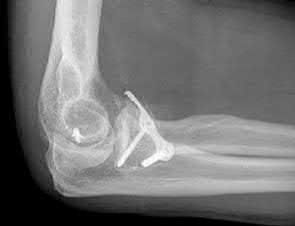

What physical exam finding is most likely to be found in association with the injury shown in Figures A and B?

The x-ray shows a fracture of the anteromedial facet of the coronoid with an intact radial head. Large anteromedial facet fractures are associated with varus posteromedial rotatory instability.

The anteromedial facet of the coronoid provides support to the medial elbow against varus stress. Varus and posteromedial force applied to the elbow results in disruption of the lateral collateral ligament (LCL) from its proximal origin. The coronoid is fractured as it is forced against the medial trochlea.

Coronoid fractures of significant size involving the sublime tubercle (insertion of medial collateral ligament) result in varus instability.

Steinmann reviews the anatomy, diagnosis, classification and treatment of coronoid fractures with a focus on surgical exposures and fixation techniques. He states that when a coronoid fracture is associated with a pattern of varus instability, it requires fixation with either suture, buttress plating or screw fixation. Concomitant LCL repair or reconstruction will also be necessary.

Doornberg et al. reviewed 67 coronoid fractures to determine whether type of coronoid fracture correlated with pattern of instability. They found strong

associations between (1) large coronoid fractures and trans-olecranon fracture-dislocations, (2) small fractures and terrible-triad injuries, and (3) anteromedial facet fractures and varus posteromedial rotational injury mechanisms.

Doornberg et al. evaluated 18 patients with a fracture of the anteromedial facet of the coronoid. They found that malalignment of the anteromedial facet fragment was associated with arthrosis and a fair or poor result.

Figure A is an AP view of an elbow with an anteromedial facet of the coronoid fractured. The lateral joint space is widened due to injury to the LCL. The medial joint space is narrowed and collapsed. A lateral view is shown in Figure

B. Illustrations A and B show AP and lateral views of a coronoid fracture fixed with buttress plating. The LCL origin was fixed with a suture anchor. Illustration C shows the O'Driscoll classification of coronoid fractures. Illustration D lists injury patterns that suggest posteromedial versus posterolateral rotatory instability.